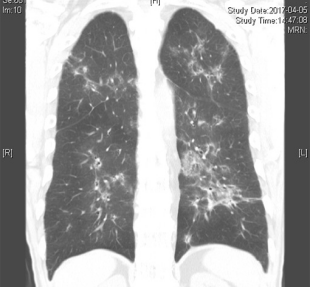

病例:男性,33岁,劳力性呼吸困难4年,加重3月,在治疗之前,我们看到的影像有些磨玻璃影、马赛克征,还有小叶中央型结节,并进行了外科肺活检。患者在从事铸造工作过程中间断接触异氰酸酯。停止工作暴露,并糖皮质激素经过治疗后,病情好转,但停用激素后又出现了肺部弥漫的磨玻璃影,肺功能也有所下降。

图:(从左至右)治疗前、脱离暴露+激素治疗10月、停激素18月